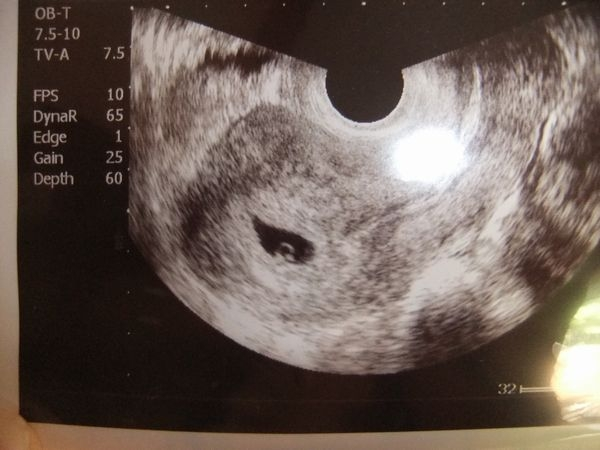

なんと、若女将のお腹の中に3人目の新しい命が誕生しました!

現在5週目で御座います

出産予定は来年の3,4月頃だと思われます